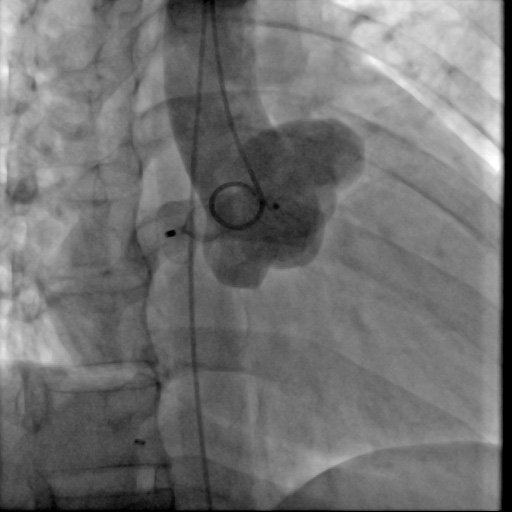

图:患者术后

“我们的治疗方案是在左冠状动脉右房瘘瘘道内放置封堵器,目的就是用封堵器把这个异常的血管通路封闭掉,这种方式创伤小、恢复快,同时也能解决患者的问题。”朱建峰介绍。

经主任蔡国才、副主任唐波和主治医师朱建峰介入团队讨论后,最终决定为患者实施创伤小、恢复快、临床效果好的冠状动脉瘘栓塞封堵术。